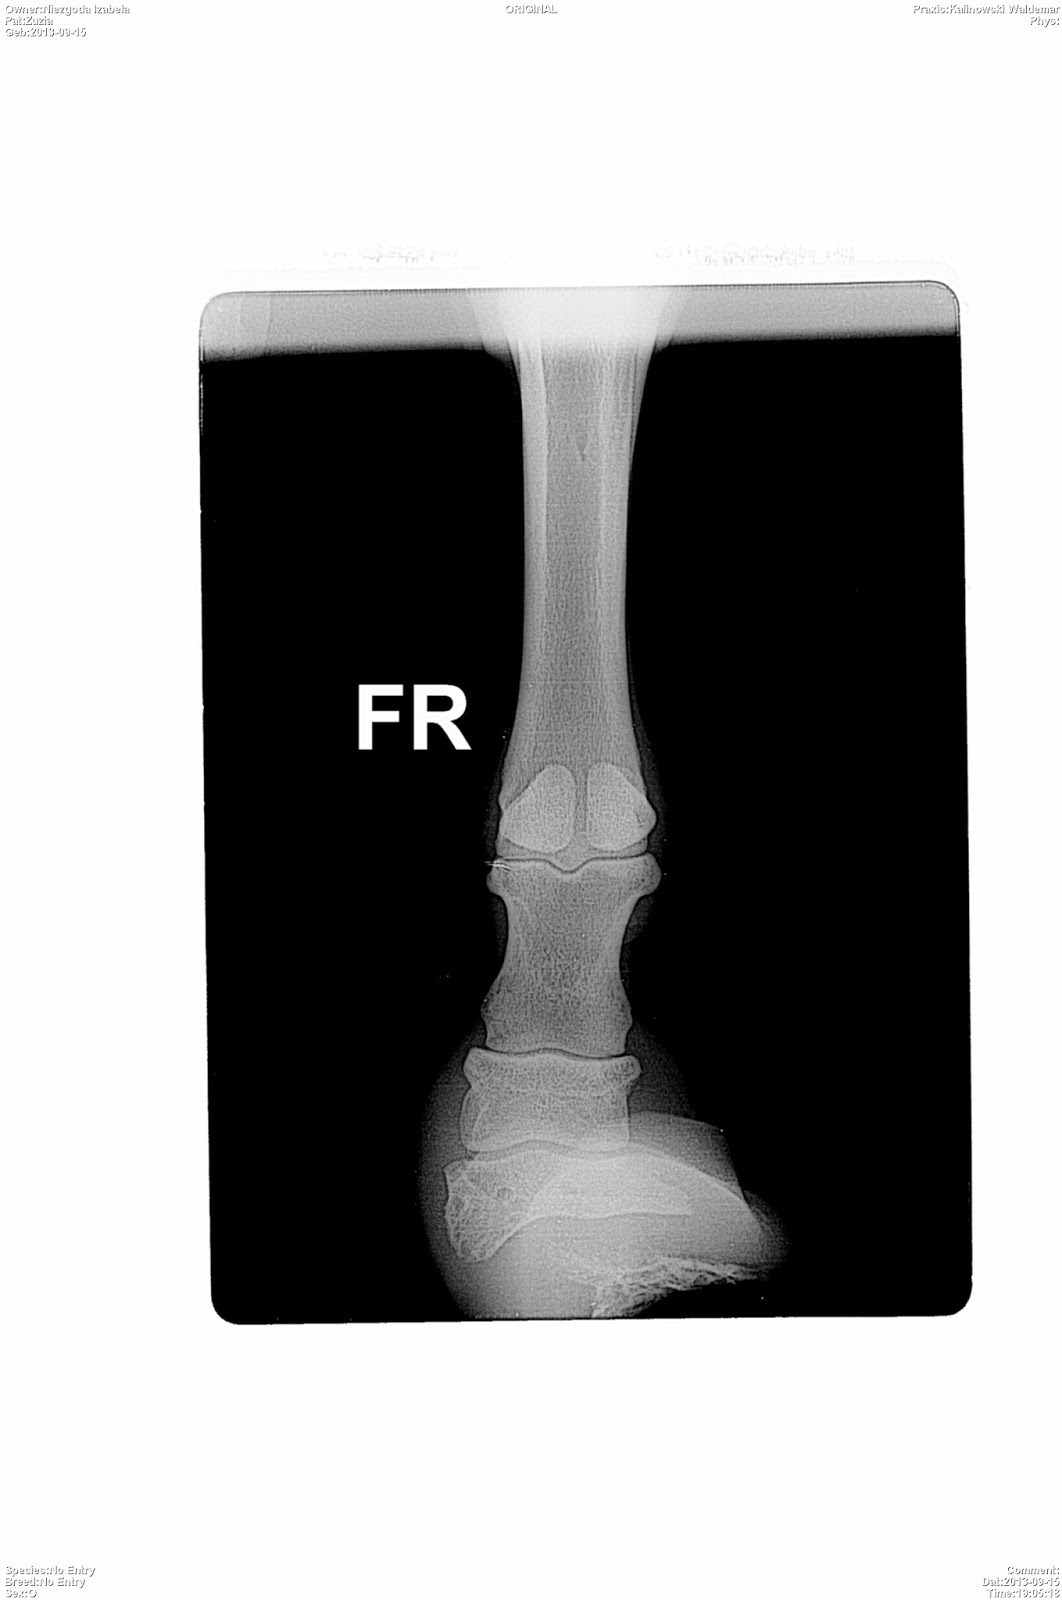

Niżej wrzuciłam zdjęcia z prześwietleń przednich nóg.

Kto jest ciekawy to niech sobie wyszuka zdjęcia/rysunki poprawnie zbudowanego kopyta i porówna.